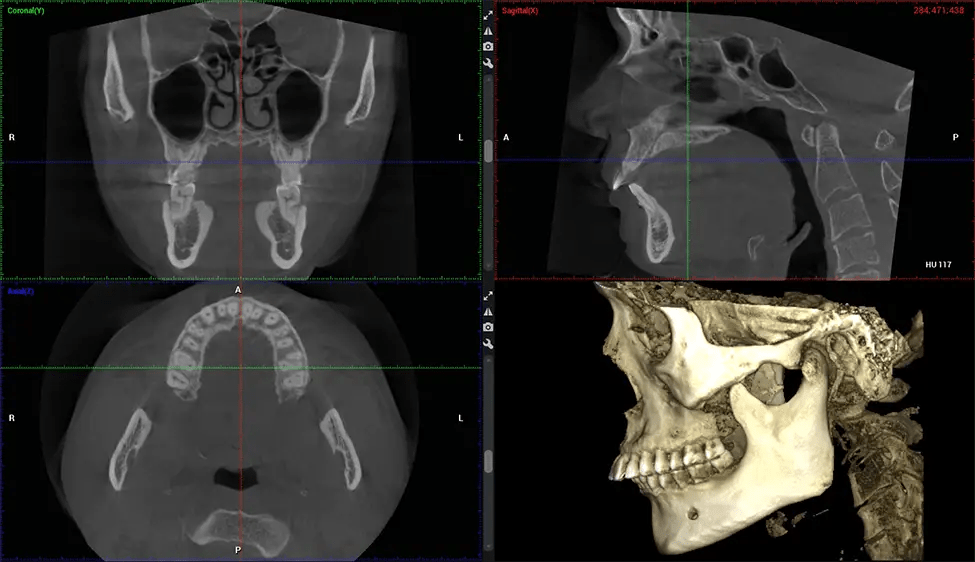

This 3D scan, called cone beam computed tomography, gives your dentist a more complete image of your oral anatomy and disease processes than a traditional X-ray. Unlike conventional X-rays, which capture a 2D image of your mouth from various angles, a 3D scan takes multiple digital X-rays for one image. It provides a complete view of your jaw, teeth, nerves, and soft tissues. This enhanced view allows dentists to detect minor issues not visible in traditional 2D scans, such as impacted wisdom teeth or bone fractures in the sinus cavity.

There are many benefits to using CBCT technology, especially compared to the traditional 2D X-ray format. One of the most significant advantages of CBCT scans is that they provide much more information than traditional X-rays. A scan lets your dentist see images from all angles of your jaw and mouth, including your sinuses, nasal cavity, cheekbones, and other surrounding areas. This added information helps your dentist craft a comprehensive treatment plan that addresses all aspects of your oral health.

Another significant benefit is that 3D imaging provides more precise images of your bone structure. These images are more detailed, providing you with a more accurate diagnosis. An accurate diagnosis means better treatment for you.

When paired with extractions, dental implant placement, or bone grafting, CBCT technology can provide you with a quicker and much more comfortable experience. This is because the 3D image provides a more detailed picture of your entire oral cavity, allowing your dentist to walk you through each step of the process before it occurs. This often helps patients feel more prepared and comfortable overall, especially if they have had a traumatic experience with past dental treatments.

After the scanning process, the captured X-ray images are processed by the CBCT software, which applies algorithms to reconstruct a detailed 3D image of the scanned area. The software compiles these individual X-ray images and creates a digital 3D representation of the patient’s anatomy. The reconstructed 3D CBCT image can be viewed and analyzed by the dentist or radiologist. This image can be manipulated, rotated, and zoomed in or out to examine specific structures and evaluate the patient’s condition.